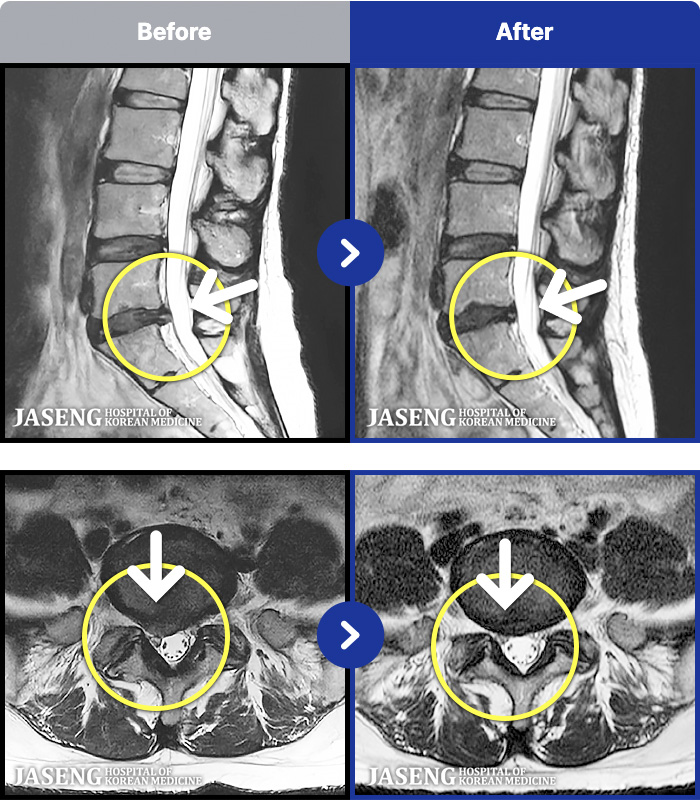

MRI ġ

MRI ũ ʸ Ȯϼ.